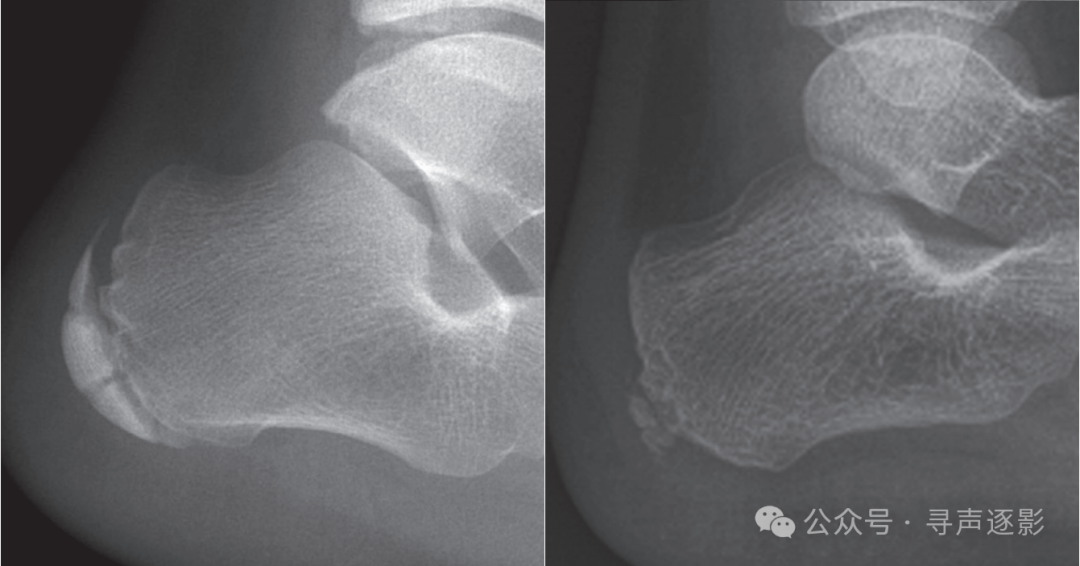

正常踝关节(左,成人;右,儿童)正位 Mortise片

正常踝关节侧位片